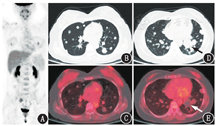

患者女,41岁,主诉检查发现双肺多发结节2个月余。患者2个月前外伤后出现意识障碍,当地医院胸部CT提示双肺多发大小不等结节,边界清楚,增强后未见明显强化。就诊于本院后查血清肿瘤标志物均正常。既往史:患者13年前行子宫肌瘤瘤体摘除术,11年前因子宫肌瘤复发行子宫切除术;8年前行左上臂脂肪瘤切除术;2个月前外伤后致右侧锁骨骨折。鉴于双肺多发结节,临床考虑不除外肺恶性转移瘤,遂行18F-脱氧葡萄糖(fluorodeoxyglucose, FDG)PET/CT显像(图1)。

18F-FDG PET/CT图像可见双肺多发大小不等的实性结节,随机分布,边缘光滑,密度均匀,较大者位于左肺下叶,直径3.1 cm,部分结节有轻度放射性摄取增高,最大标准摄取值(maximum standardized uptake value, SUVmax)1.3,低于纵隔血池(SUVmax 1.8);右侧锁骨骨皮质不连续,局部伴骨痂形成,相应部位放射性摄取增高,SUVmax 2.1,考虑为骨折后修复改变;右侧卵巢大小正常,放射性摄取增高,SUVmax 3.6,考虑为生理性摄取;其余部位未见明确代谢异常病灶。